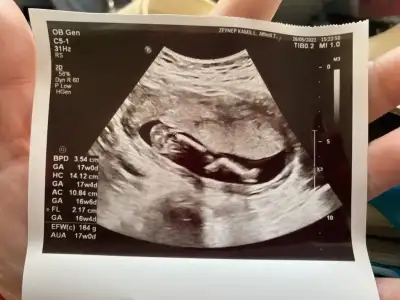

Merhaba 17+0 haftalık karından ultrason görüntüsü tahmin edebilir misiniz bizim minnak cinsiyetini hala saklıyor 🥰